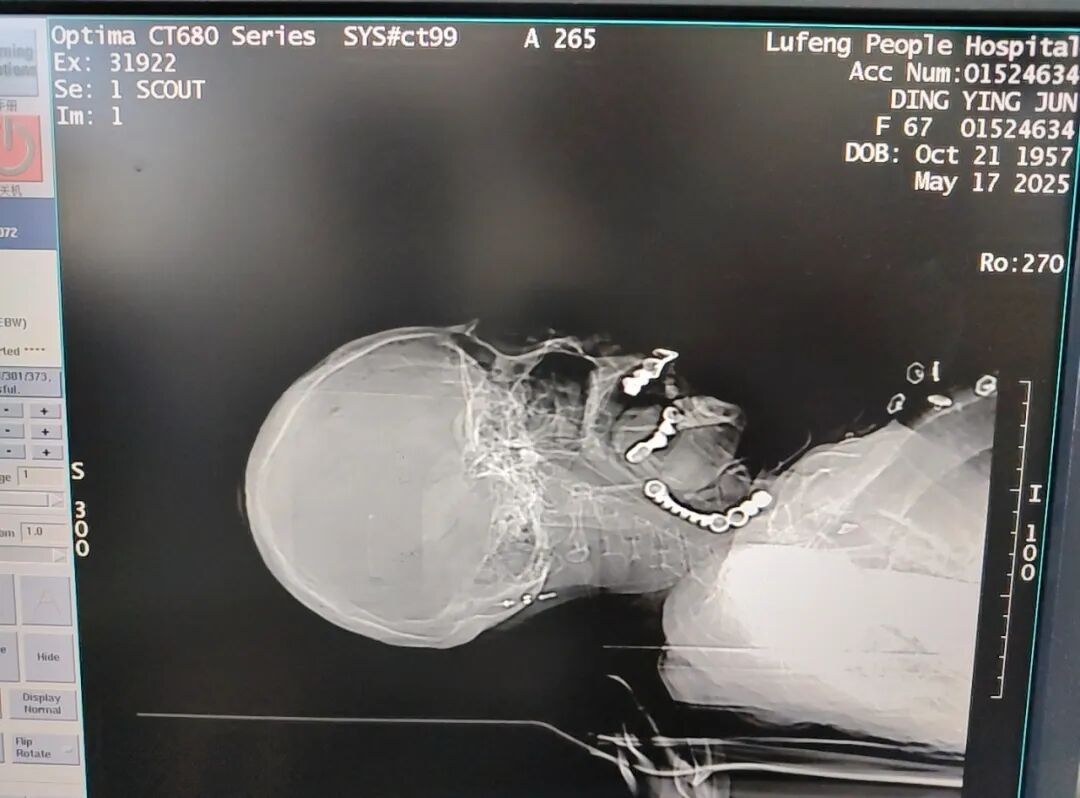

急诊医生检查发现患者呼吸急促,神情痛苦双肺听诊湿性啰音连接床边心电监护提示血氧饱和度数值仅 82%(正常需≥95%)。CT 影像结果令人揪心:患者气管声门处竟存在一环形异物,直接堵塞气道,这正是导致呼吸困难、血氧下降的核心原因!

▲CT显示气管异物